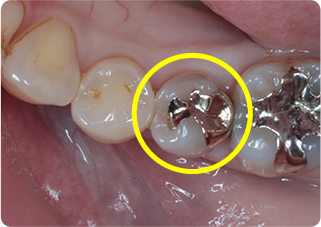

セラミックアンレー症例④

術前

インレー除去

ラバーダム防湿

シリコン印象

技工物

術後

| 主訴 | 右上奥歯の銀歯に食べ物が挟まる |

|---|---|

| 治療期間/回数 | 2週間、2回 |

| 価格(税込) | 77,000円(税込) |

| リスク・副作用 | セラミックの破損、一時的な知覚過敏が生じる場合がある |

| ポイント | 銀歯の詰め物の中がむし歯になっていたため、う蝕検知液を使用し選択的にむし歯のみを除去。またセラミック装着時にラバーダム防湿を行うことで、詰め物の接着効果を最大限発揮できるようにした。 |